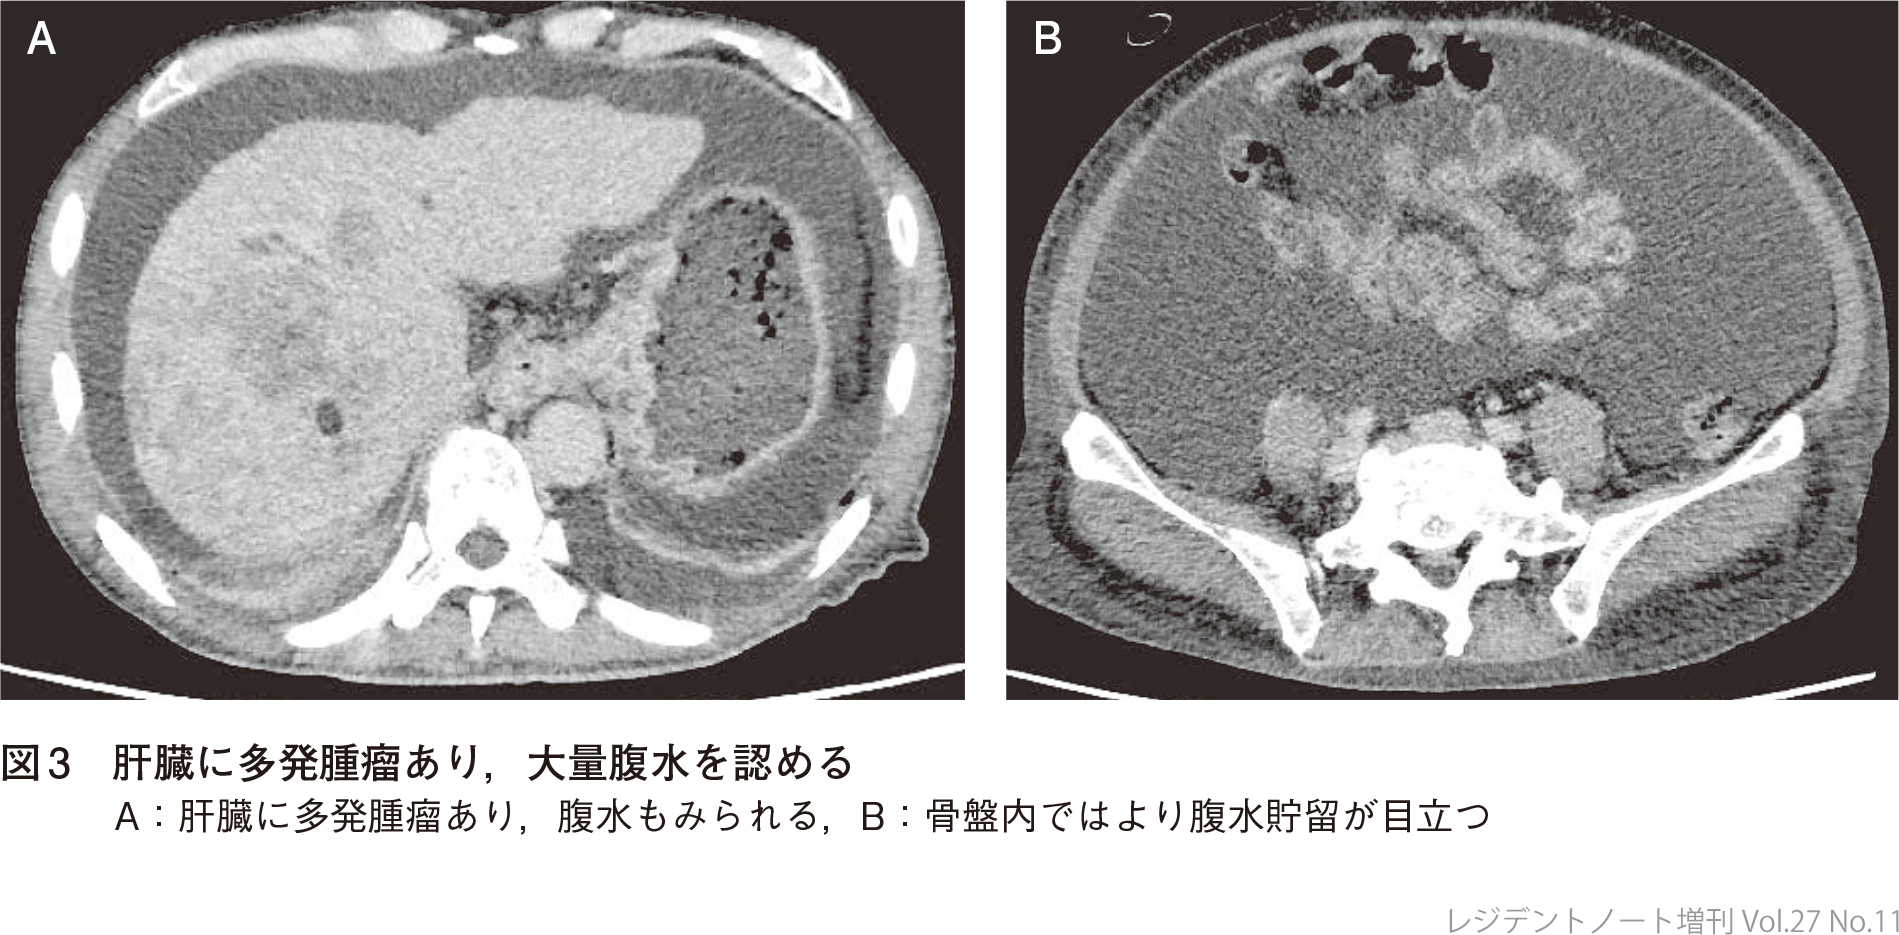

70歳男性.転移進行肝内胆管がんに対して,デュルバルマブ+シスプラチン+ゲムシタビンで治療中.治療開始して約6カ月後の外来で食欲低下と腹部膨満の訴えあり,CT検査では大量腹水を認めた(図3).

SAAGは0.1 mg/dLで,非門脈圧亢進パターン.腹水細胞診で悪性所見はみられなかったが,CT検査で多発肝転移が増大したタイミングでもあり,がん性腹膜炎の関与が疑われた.直後に胆管炎を発症してPerformance Status低下みられたことから,本人および家族と相談してBest Supportive Care方針となった.